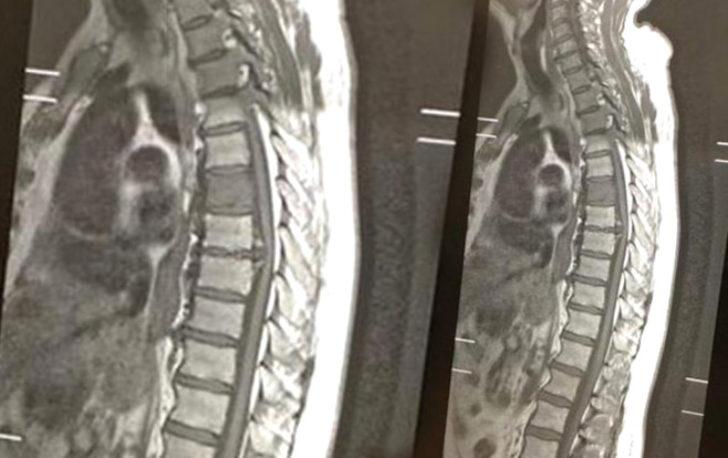

Yemek borusu kanseri sebebiyle 3 yıl boyunca tedavi görmek durumunda kalan 70 yaşındaki Peter Cavanagh, hastalığının nüksetmesi sebebiyle tekrar tedavi sürecine başladı. Omurgasını da etkileyen rahatsızlığından dolayı röntgen çektiren yaşlı adam, sonucu gördüğünde 50 yıllık eşi Tess ile birlikte gülmeye başladı.

Çünkü röntgen filminde 'cocker spaniel' cinsi bir köpeğin sureti gözüküyordu. Bu büyük bir tesadüften başka bir şey değildi. Görüntü hakkında şakalar yapan yaşlı adam, İngiltere gazetelerinde gündem oldu. Peter Cavanagh, "Ailemle köpeğin cinsinin beagle mı, spaniel mı olduğunu tartıştık ama bence kesinlikle spaniel. Burnu tam olarak, kanserin vücudumu etkilediği yerde" dedi.